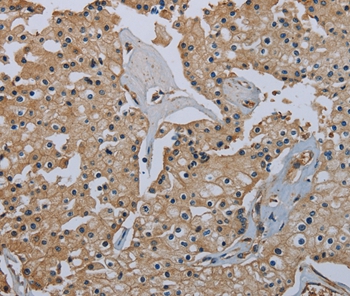

Immunohistochemical analysis of paraffin-embedded Human prostate cancer tissue using #36486 at dilution 1/40.

Immunohistochemical analysis of paraffin-embedded Human brain tissue using #36486 at dilution 1/40.